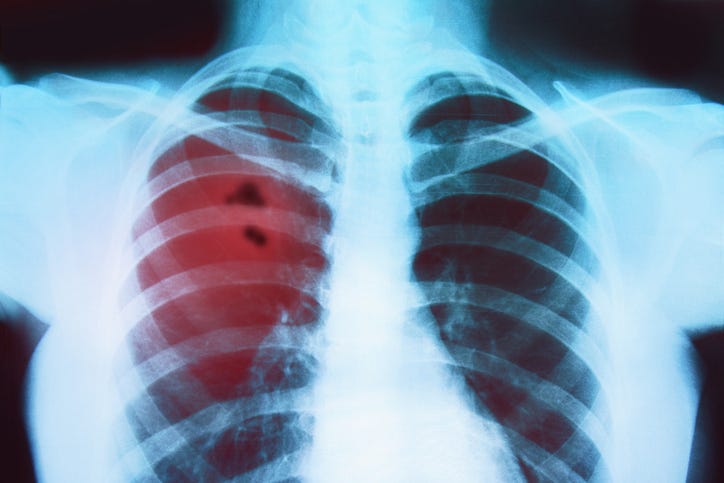

A new report says Louisiana ranks among the worst states in the nation for detecting lung cancer early. The findings are in the State of Lung Cancer Report. Ashley Lyerly is the Director of Advocacy for the American Lung Association.

The report found Louisiana ranked 45th in the nation for early diagnosis and 41st for surviving lung cancer. But she says it’s not all bad news. She says there are fewer cases than in the past and the five-year survival rates are better. She says smoking is still the number one cause of lung cancer, and there is a stigma associated with it.